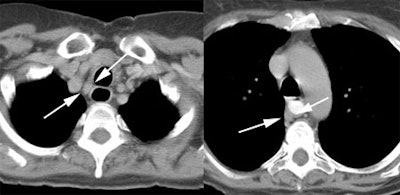

Response to therapy: This is the patient shown in the case above with progressive dysphagia and a large distal esophageal mass with gastrohepatic ligament adenopathy. Note the decreased uptake within the primary mass (arrowhead) and gastrohepatic nodes following initiation of radiation therapy. However, new uptake can be seen in two lymph nodes (black arrows) which were not identified prospectively on post-therapy CT imaging (white arrows on CT). The findings are concerning for metastatic disease and the patient went on to receive additional chemotherapy with subsequent resolution of the nodal uptake. |